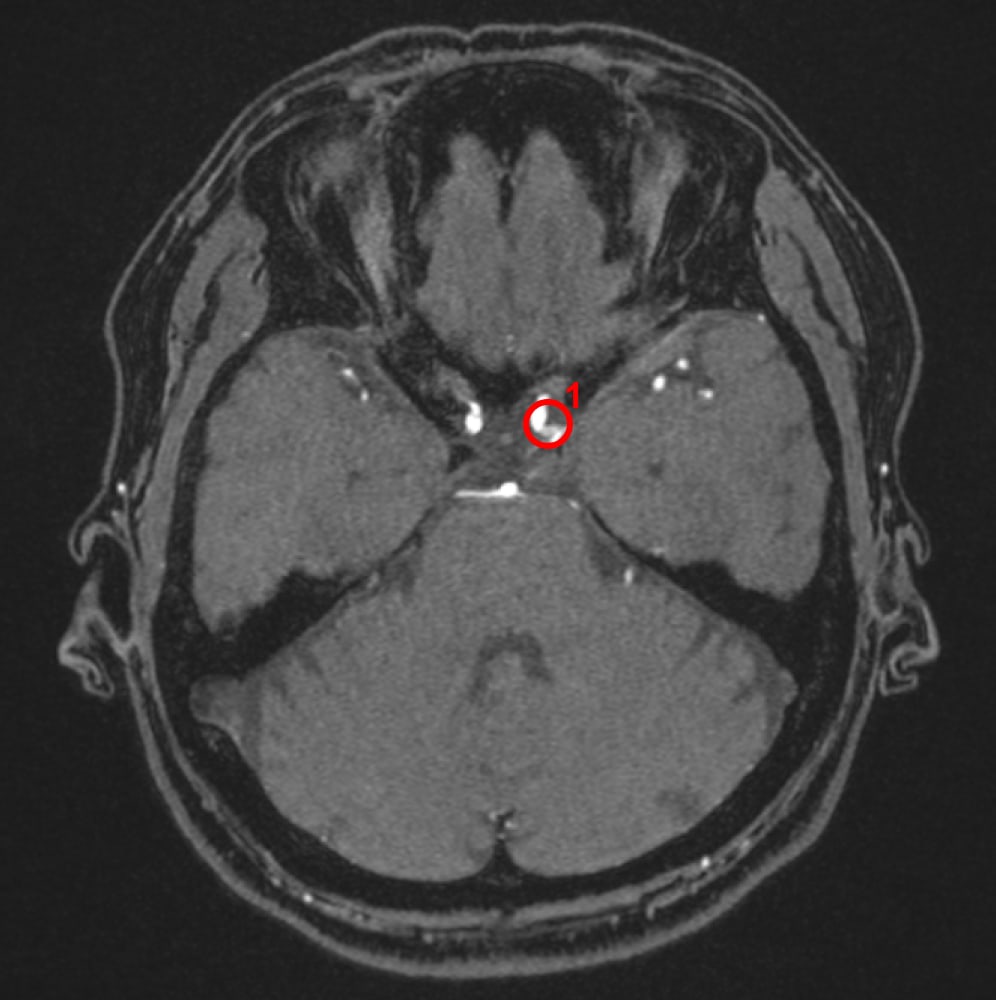

解析事例

内頚動脈-後交通動脈